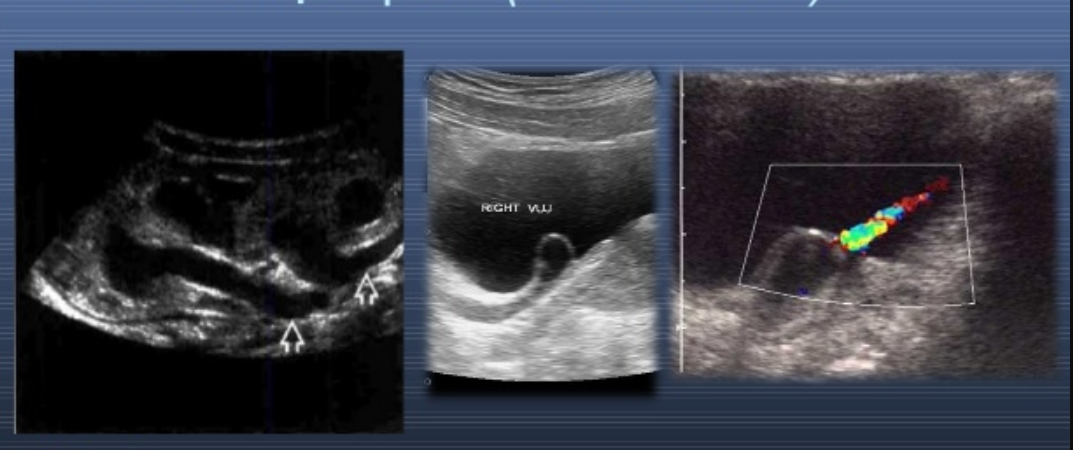

Túi sa niệu quản là một bệnh bẩm sinh, khiến cho niệu quản bị giãn nở và hình thành một túi. Bệnh này thường được phát hiện ở trẻ sơ sinh và trẻ nhỏ, nhưng cũng có thể ảnh hưởng đến người lớn.